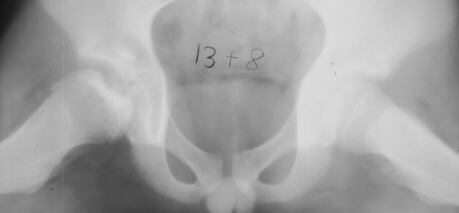

The parents first noted at the time the patient was 10y and 9 m old that he would limp on the right side after a full day of activity. He also started to have a occasional hip pain. Since the hip pain became progressively worse, he visited local clinics and was referred to AIDI at the age of 11y and 3 m. At the first examination abduction was 40 degrees bilaterally but internal rotation was limited to 0 degree on the right. The leg lengths were equal and no Trendelenburg sign was observed. X-ray showed the decreased epiphyseal height and medial joint opening. Snyder sling was started. At 12 years of age, internal rotation was still limited 20 degrees compared to 35 degrees on the left side but the left hip pain was asymptomatic. At 13 years of age, X-ray showed the regenerated head, so the Snyder sling was stopped and weight bearing was started. The Snyder sling had been applied for 2 years. At 16 years of age, ten degrees limitation of internal rotation as compared to the opposite side was still observed but the patient was asymptomatic.

11 yrs 3 mos, , 12 yrs, 13 yrs 8 mos , 17 yrs , 18 yrs.